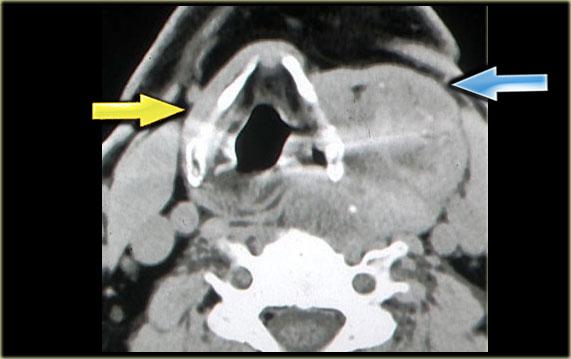

Bên trái là hình CT ở mức sụn giáp.

Có một khối không đều nằm trung tâm ở xoang lê bên phải.

Khối này nằm trong khoang tạng.

Ở vùng này, khối u thường gặp nhất là ung thư biểu mô tế bào vảy.

Chẩn đoán này đã được xác nhận qua sinh thiết.

Lưu ý khoang sau hầu (mũi tên vàng).

Đây là khoang ảo chỉ chứa một ít mô mỡ.